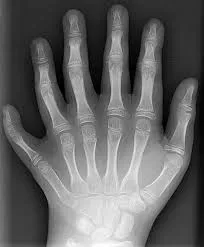

ଉତ୍ତର ପ୍ରଦେଶ ଅନ୍ତର୍ଗତ ବାରବାଙ୍କିରେ ଗୋଟାଏ ବାଳକ ହାତରେ ୧୨ଟି ଓ ଗୋଡ଼ରେ ୧୨ଟି ଆଙ୍ଗୁଠି ଥିବାରୁ ତାର ଦିନ ଭଲରେ କଟୁନାହିଁ। ପିତାମାତାଙ୍କ କହିବାନୁସାର,ଜଣେ ତାନ୍ତ୍ରିକଙ୍କ ପରାମର୍ଶ କ୍ରମେ ଆତ୍ମୀୟ ସ୍ୱଜନମାନେ ତାକୁ ମାରି ଦେବାକୁ ଚାହୁଁଛନ୍ତି। ଏଭଳି ଶାରୀରିକ ବିକୃତି ଥିବା ପିଲାକୁ ବଳି ଦେଲେ ସେମାନେ କୁଆଡ଼େ ବିତ୍ତଶାଳୀ ହୋଇଯିବେ ବୋଲି ସେମାନେ ମାନୁଛନ୍ତି ।ବାପା କହନ୍ତି: ଆମେ ତାକୁ ସ୍କୁଲକୁ ଛାଡୁନାହୁଁ। ପୁଲିସର ସହାୟତା ମଧ୍ୟ ଲୋଡ଼ିଛୁ।